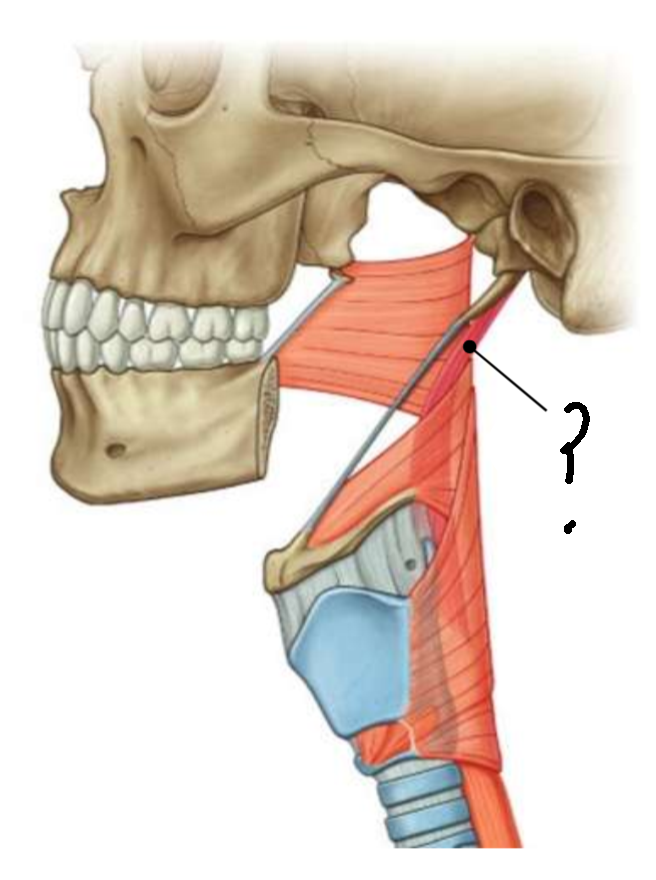

What is in the rectangle?

pterygomandibular raphe

What is this muscle?

stylopharyngeus

What are the attachments of this muscle?

medial surface of the styloid process → deep pharyngeal wall

What innervates this muscle?

glossopharyngeal nerve

What muscle is this?

palatopharyngeus

What are the attachments of this muscle?

upper surface of palatine aponeurosis → deep pharyngeal wall

What is the function of this muscle?

closes the oropharyngeal isthmus by depressing the palate